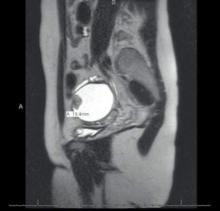

MRI view of an endometrioma with a malignant mural nodule. Courtesy Dr. Farr Nezhat

MRI view of an endometrioma with a malignant mural nodule.